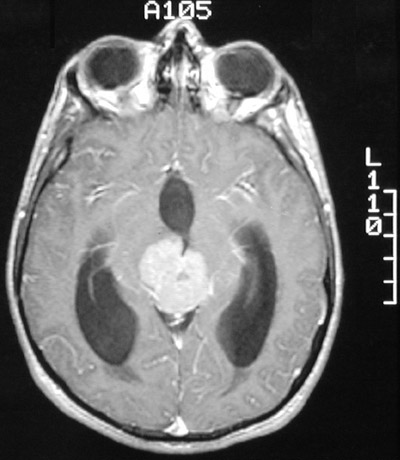

This enhanced MRI scan in axial view reveals a

mass in the region of the pineal

. This is a germinoma. The enlarging mass has occluded the fourth ventricle and led to hydrocephalus.